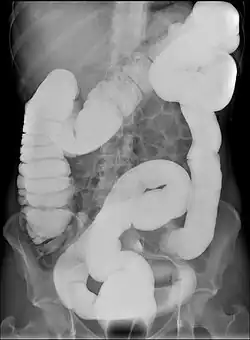

Dolichocolon also known as redundant colon or tortuous colon is an abnormally long large intestine.[1] It should not be confused with an abnormally wide large intestine, which is called a megacolon.

Dolichocolon may predispose to abnormal rotation (see volvulus) and interposition between the diaphragm and the liver (see Chilaiditi syndrome). It is a congenital condition.[2] The exact cause remains unknown. Dolichocolon is often an incidental finding on abdominal X-rays or colonoscopy. It is not by itself a disease and as such requires no treatment. The term is from ancient Greek dolichos, the long distance in running, and colon.